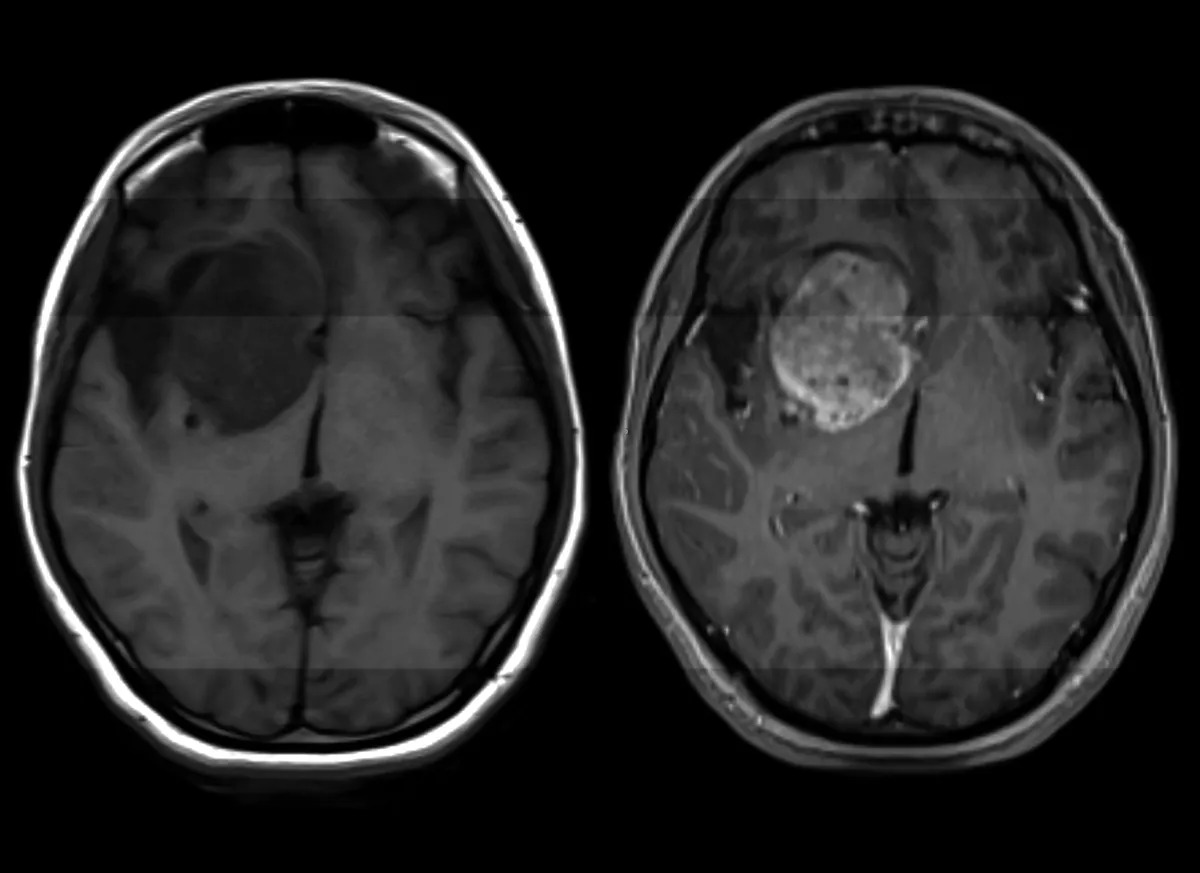

Një zbulim i ri shkencor në kuptimin e patologjisë së glioblastomës — forma më e zakonshme dhe njëkohësisht më agresive e kancerit të trurit, e cila aktualisht konsiderohet e pashërueshme — ka hapur perspektiva të reja për zhvillimin e një trajtimi të ardhshëm që, në parim, mund të jetë po aq i thjeshtë sa marrja e një pilule.

Vetëm në Shtetet e Bashkuara, çdo vit më shumë se 14,000 persona diagnostikohen me glioblastomë. Ky tumor i trurit është jashtëzakonisht agresiv, i paparashikueshëm dhe rezistent ndaj trajtimeve ekzistuese. Pacientët e diagnostikuar rishtazi jetojnë mesatarisht vetëm 12 deri në 18 muaj, edhe me trajtim; pa ndërhyrje mjekësore, kjo kohë do të ishte edhe më e shkurtër. Vetëm rreth 5% e pacientëve arrijnë të mbijetojnë pesë vjet pas diagnozës.